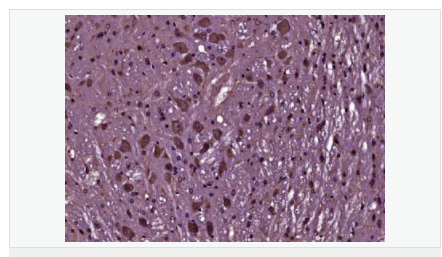

首頁>>免疫學>>一抗>>磷酸化Bcl-2抗體

磷酸化Bcl-2抗體

Rabbit anti-Phospho-Bcl-2 (Thr129) Polyclonal antibody

英文名稱Phospho-Bcl-2 (Thr129)

中文名稱磷酸化Bcl-2抗體

產(chǎn)品介紹BCL2 is an integral outer mitochondrial membrane protein that blocks the apoptotic death of some cells such as lymphocytes. Constitutive expression of BCL2, such as in the case of translocation of BCL2 to Ig heavy chain locus, is thought to be the cause of follicular lymphoma. Two transcript variants (alpha and beta) produced by alternate splicing, differ in their C-terminal ends. BCL2 suppresses apoptosis in a variety of cell systems including factor-dependent lymphohematopoietic and neural cells. It regulates cell death by controlling the mitochondrial membrane permeability. It appears to function in a feedback loop system with caspases. BCL2 inhibits caspase activity either by preventing the release of cytochrome c from the mitochondria and/or by binding to the apoptosis-activating factor (APAF1). It can form homodimers, and heterodimers with BAX, BAD, BAK and BclX(L). Heterodimerization with BAX requires intact BH1 and BH2 domains, and is necessary for anti-apoptotic activity.